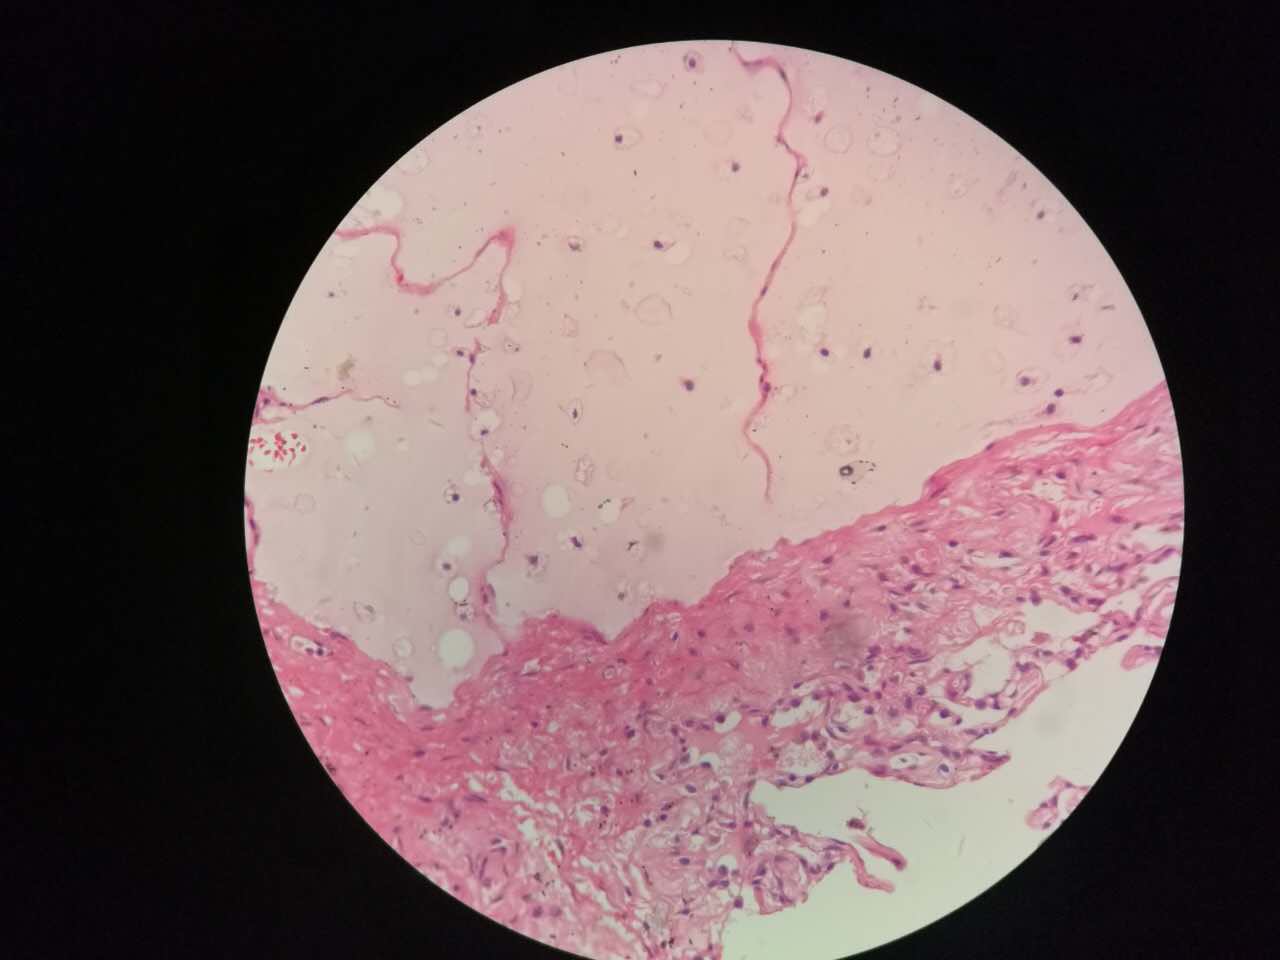

这个是早期结节状的粘液型腺癌

随着粘液近距离播散

早期粘液漂散也是近距离的,右侧肺泡里干净,没粘液,粘液产量有限,并且互相有黏连牵制。

所以结节性粘液腺癌边界一般较清楚